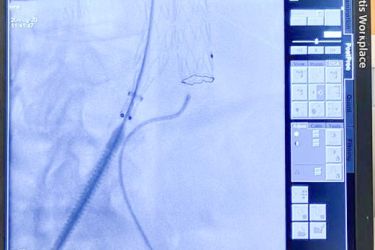

Этот вид операции позволяет через два небольших разреза на бедре, под видеоконтролем, проникнуть по сосудам в аорту и заменить ее поврежденный участок изнутри. Сосудистый протез, уложенный в специальную систему, доставляется до места АА, расправляется прямо в полости аневризмы. Всю процедуру осуществляет врач-эндоваскулярный хирург под контролем рентген-установки. Таким образом, протез берет на себя силу воздействия системного артериального кровотока на слабые растянутые стенки аорты.